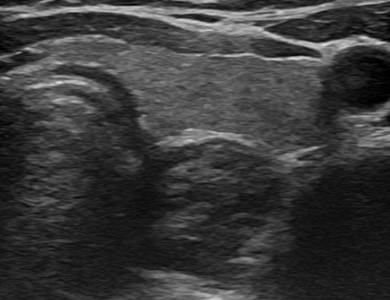

ÃÊÀ½ÆÄ »çÁø

ÁÂÃø °©»ó¼± ¾ç¼º °áÀý

img